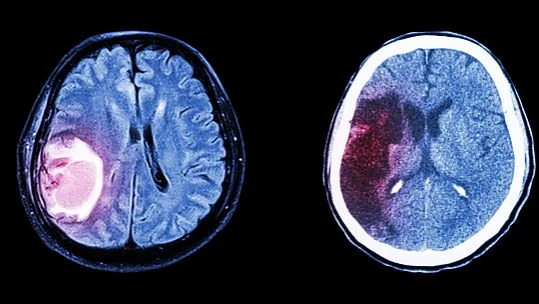

接下来,医生通常会建议进行脑部影像学检查,例如CT或MRI。这些检查能够明确肿瘤的位置、大小及对周围结构的压迫情况,是目前诊断桥小脑角区脑膜瘤的主要手段。据《美国神经外科学会杂志》的一篇报道,MRI在软组织分辨率上有明显优势,能够更清晰地显示桥小脑角区的解剖结构。

如果你出现了听力减退、头晕、面部麻木等症状,且经常频繁发作,就应该及时去医院进行检查。医生会通过影像学检查(例如CT和MRI)来确认肿瘤的位置和大小,以进行下一步的治疗方案制定。